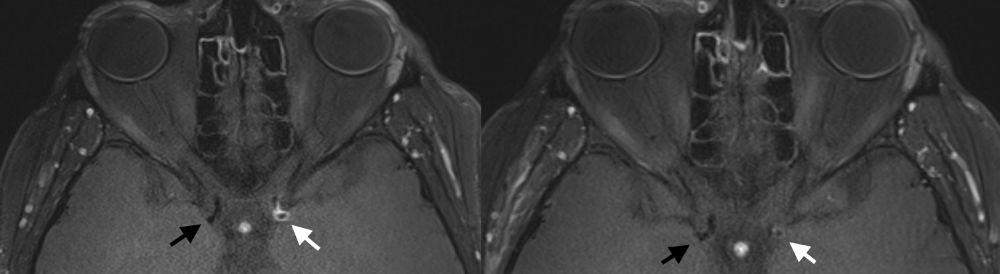

Funktionelles MRT (breath-hold fMRI)

In der konventionellen Angiographie und im konventionellen MRT können selektiv die Gefäße, der Blutfluss, und das Gewebe gut dargestellt werden. Diese Untersuchungen erbringen jedoch keine Aussage über den absoluten Blutfluss im Gehirn. Adaptierte Untersuchungen des MRTs, sowie auch des CTs zur Messung der Hirndurchblutung (Perfusion) haben sich in der Vergangenheit bei Moyamoya Betroffenen auf Grund der Kollateralen als zu wenig sensitiv gezeigt, um die Durchblutung zuverlässig darzustellen.

Durch die Erforschung und Weiterentwicklung des funktionellen MRTs haben wir eine Untersuchung etabliert, welche die Reaktivität der Hirngefäße (und somit indirekt die cerebrale Durchblutungsreserve) darstellen kann. Beim sogenannten "breathhold", also Atemanhalte-fMRT müssen die Patientinnen und Patienten in mehreren Zyklen für jeweils wenige Sekunden die Luft anhalten. Dadurch erhöht sich die CO2-Konzentration im Blut und die Hirngefäße stellen sich weiter. Diese Veränderung des Blutflusses kann dann indirekt gemessen werden. Da es sich hierbei um eine sehr neue Methode handelt, ist zu erwähnen, dass medizinische Entscheidungen primär ausschließlich in Zusammenschau aller Befunde und bei jeglicher Unschlüssigkeit mit dem ergänzenden PET/CT getroffen werden. Das fMRT hat sich jedoch als exzellentes Screening-Tool und für die langfristigen Nachkontrollen erwiesen.